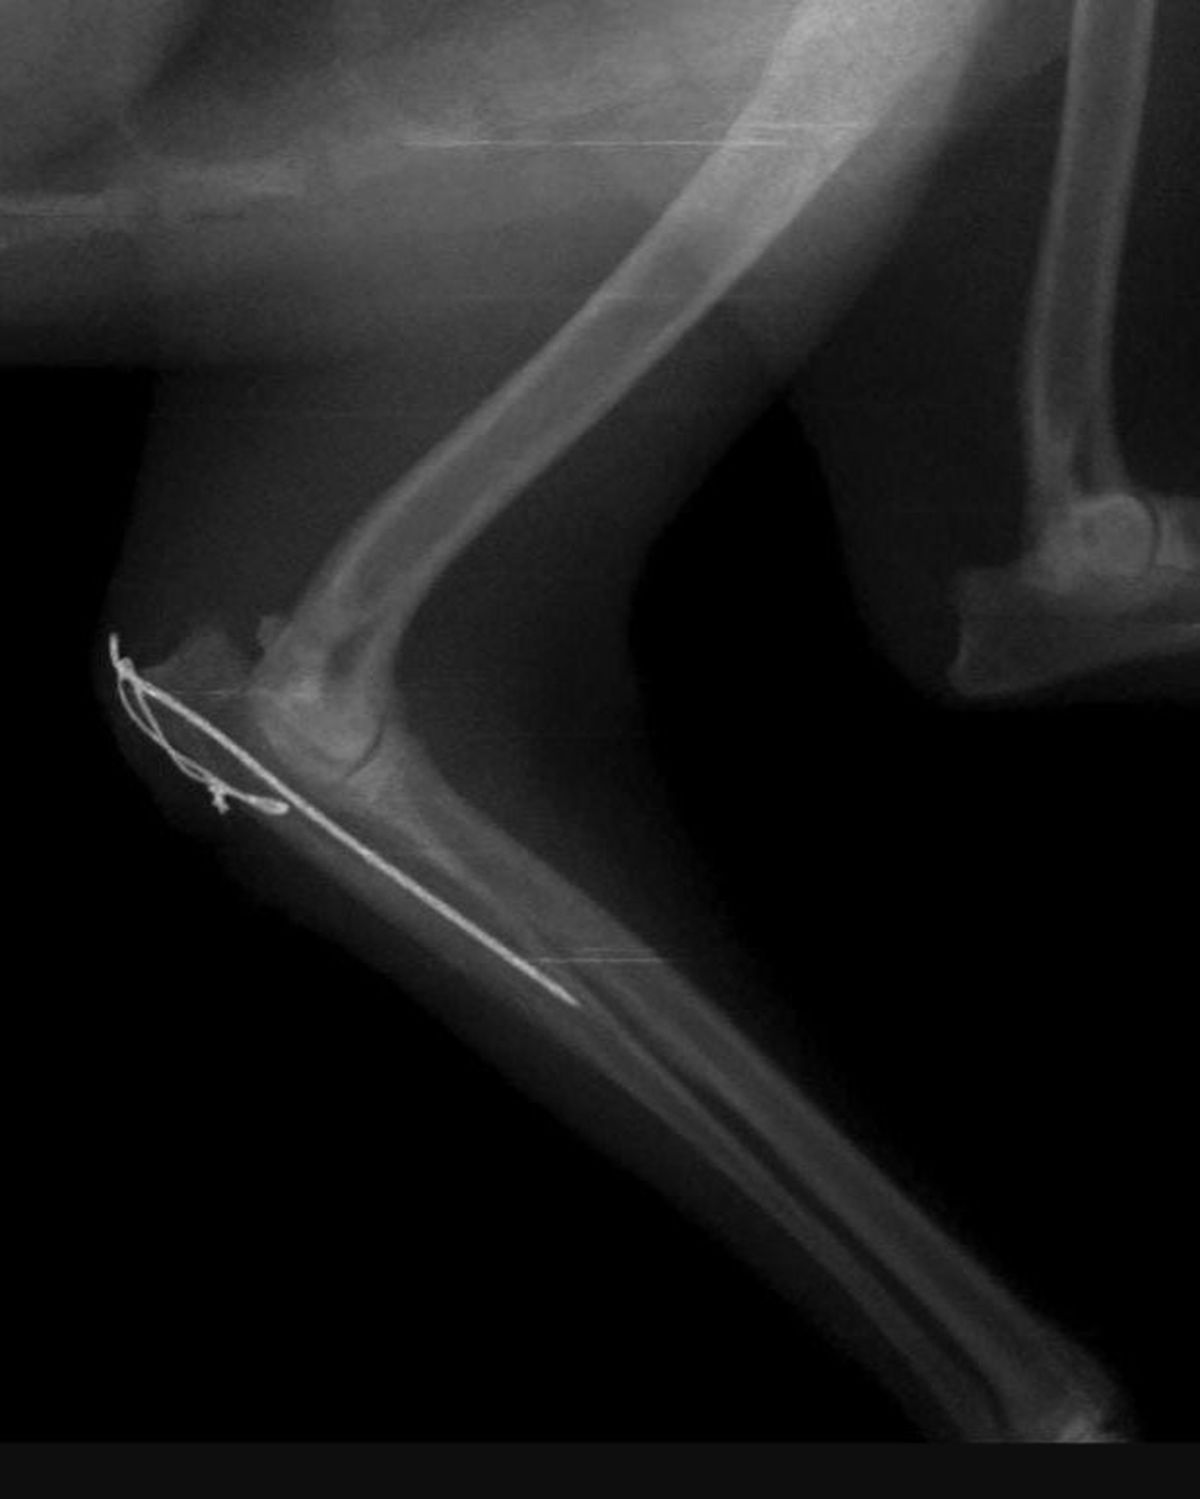

El rescate de fauna silvestre llevado adelante por el Ministerio de Ambiente y Cambio Climático de Jujuy permitió salvar la vida de una hembra adulta de zorro colorado (Lycalopex culpaeus), que fue atropellada en inmediaciones del Parque Nacional Laguna de Pozuelos, en la zona de Abra Pampa, y recibió atención veterinaria especializada.

A través de un operativo de rescate de fauna silvestre, se logró asistir a un zorro colorado herido tras un atropellamiento en Abra Pampa.